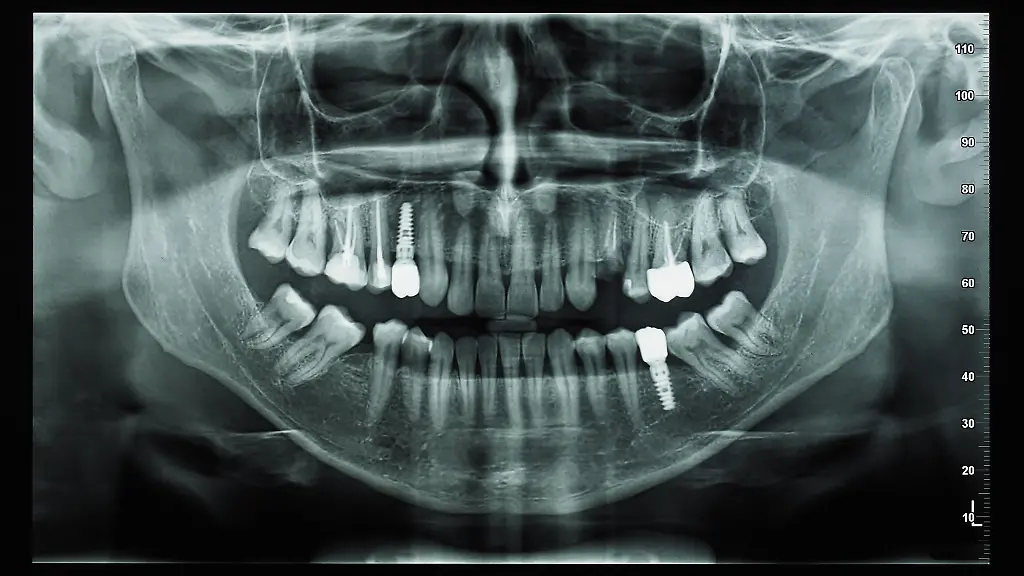

Für einen Mann in der Türkei hat eine Behandlung beim Zahnarzt mit einer Notoperation geendet. Der Arzt habe dem Patienten ein Implantat einsetzen wollen und dabei eine Schraube versehentlich in das Gehirn des Mannes gebohrt, berichtete die türkische Nachrichtenagentur IHA. Der Mann überlebte. Er habe vor Schmerz geschrien, nachdem der Arzt ihm durch den Kiefer gebohrt habe, sagte der 40 Jahre alte Patient laut IHA.

Der Arzt mit Sitz im Kreis Nilüfer in der Provinz Bursa habe ihn geröntgt, den Fehler festgestellt und ihn umgehend selbst in ein Krankenhaus gefahren. Danach sei er verschwunden. In einer mehrstündigen Operation sei die Schraube entfernt und der Patient gerettet worden, schrieb IHA. Der Fabrikarbeiter und zweifache Vater sagte, er habe rechtliche Schritte gegen den Arzt eingeleitet, der ihm bisher eine Erstattung der Behandlungskosten verweigere.

Türkischen Medien berichtete er, dass der Arzt vor dem Setzen der Implantatschraube einem Mitarbeiter gesagt habe, dass ein dafür nötiges Instrument kaputt sei. Dann habe er die Behandlung manuell fortgesetzt. Der Familienvater im Zahnarztstuhl habe gespürt, wie der Arzt sich mit viel Druck in die zu setzende Schraube gestemmt habe. Er habe dem Arzt berichtet, dass er Knochengeräusche vernehme. Der wiederum habe gesagt, dies sei normal. Dann sei die Schraube beim Hineindrücken aber durch den Kieferknochen gebrochen und hinter der Augenwand in den Bereich eingedrungen, in dem sich die Gehirn-Rückenmarks-Flüssigkeit befindet. So die Erinnerungen des Patienten. Der beschuldigte Arzt äußert gegenüber türkischen Medien, dass der Vorfall sich aufgrund einer medizinischen Komplikation ereignet habe.